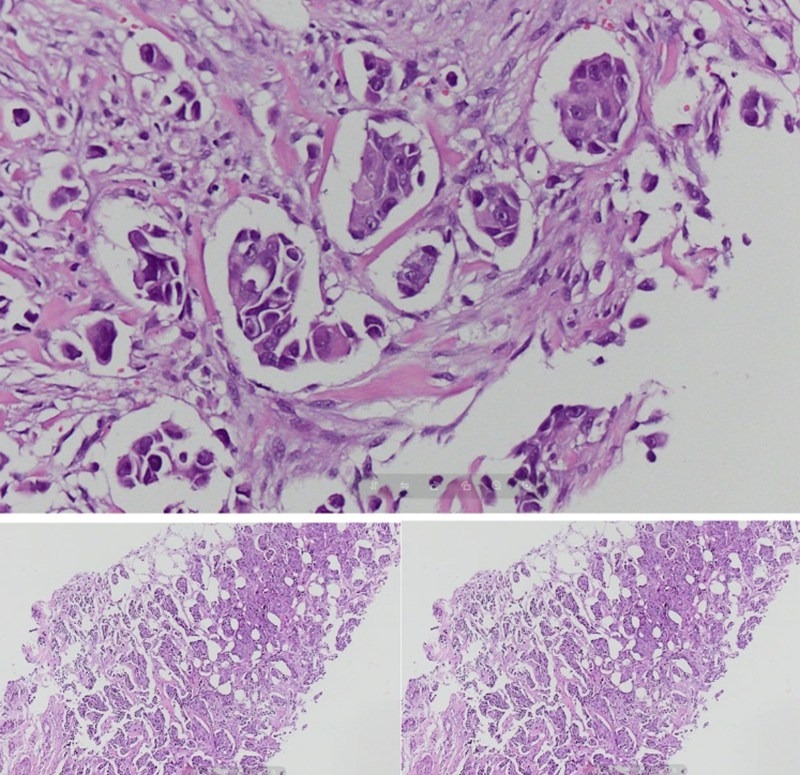

| Xét nghiệm mô bệnh học xác định bệnh nhân mắc Carcinoma tuyến vú thể ống xâm nhập |

Kết quả mô bệnh học thường quy với nhuộm Hematoxylin Eosin xác định bệnh nhân mắc carcinoma tuyến vú thể ống xâm nhập, độ mô học II. Nhằm đánh giá tiên lượng và xây dựng phác đồ điều trị tối ưu, các bác sỹ tiếp tục thực hiện xét nghiệm hóa mô miễn dịch với bốn dấu ấn ER, PR, HER2 và Ki 67.

Kết quả cho thấy khối u thuộc phân típ phân tử lòng ống B, HER2 dương tính 3+, được chẩn đoán là carcinoma tuyến vú xâm nhập, biểu mô thể ống, độ mô học II.